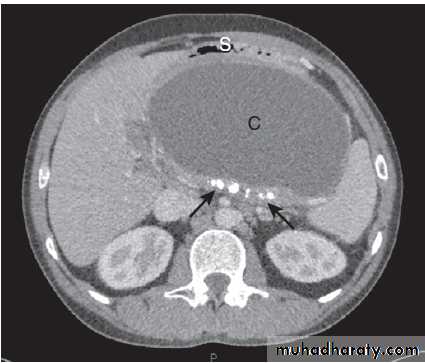

A Non-ionic contrast swallow shows leakage of contrast (arrow) into the mediastinum following stricture dilatation. B Barium follow-through. There are multiple diverticula (arrows) in this patient with jejunal diverticulosis. C Barium enema showing severe diverticular disease. There is tortuosity and narrowing of the sigmoid colon with multiple diverticula (arrows).Imaging in gastroenterology :Examples of ultrasound, CT and MRI. A Ultrasound showing large gallstone (arrow) with acoustic shadowing. B Multidetector coronal CT showing large solid and cystic malignant tumour in the pancreatic tail (arrow). (PV = portal vein; L = liver) C Pelvic MRI showing large pelvic abscess (arrow) posterior to the rectum in a patient with Crohn’s disease. D Fused CT-PET image showing two liver metastases (arrows).